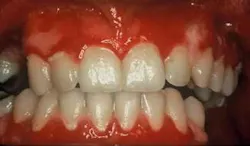

Clinical impressions: As you begin your oral assessment, you note the buccal mucosa and gingiva are erythematous with some ulceration and erosion. The erythema is very prominent at most marginal gingival areas. The tissue bleeds with very little pressure (see figure 1). You also notice that his lips appear ulcerated and crusted (see figure 2).

Early treatment is crucial in controlling pemphigus vulgaris. Sirois, et al. (2000) reported that more than 50 percent of patients in their study sought initial care from their dental clinician. Just as pemphigoid (March 2007) is often characterized as desquamative gingivitis (a general term), this is true also for pemphigus vulgaris depending upon the severity of the disease. The tissue involved is erythematous and ulcerated (see figure 1). Bullae may be present and they rupture to form painful erosions. The borders of the erosions are often ragged and painful. Depending upon the type of pemphigus, the lesions may appear to have vegetations or scales on the surface.